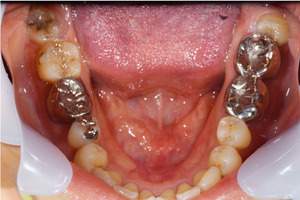

患者様の初診時レントゲン写真

歯周病の治療の必要性

ブラッシング方法の教授